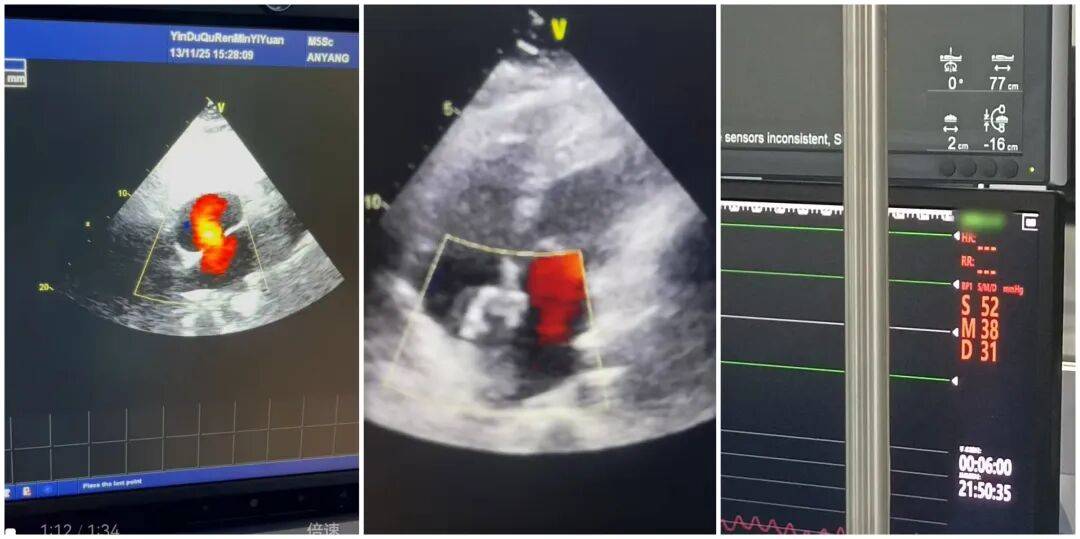

2025年11月14日,殷都區(qū)人民醫(yī)院心血管內(nèi)科團隊順利為39歲患者路女士完成房間隔缺損封堵術(shù)。此次手術(shù)的成功實施,不僅為患者解除了心臟健康隱患,更填補了本院在先天性心臟病介入治療領(lǐng)域的一項空白,為區(qū)域內(nèi)同類患者帶來了就近就醫(yī)的新選擇。

患者入院后,心血管內(nèi)科團隊高度重視,立即組織多學科會診,結(jié)合心臟超聲、心電圖等詳細檢查結(jié)果,與特邀專家共同研判病情,制定了精準的個性化手術(shù)方案。11月14日手術(shù)當天,經(jīng)右心導管檢查顯示,路女士的肺動脈壓已高達52mmHg,需盡快干預。在團隊的密切配合與專家的精準指導下,手術(shù)歷時36分鐘順利完成,成功對其直徑約25mm的室間隔缺損進行封堵。術(shù)后即刻超聲檢查證實,缺損處無過隔血流,手術(shù)效果達到預期。